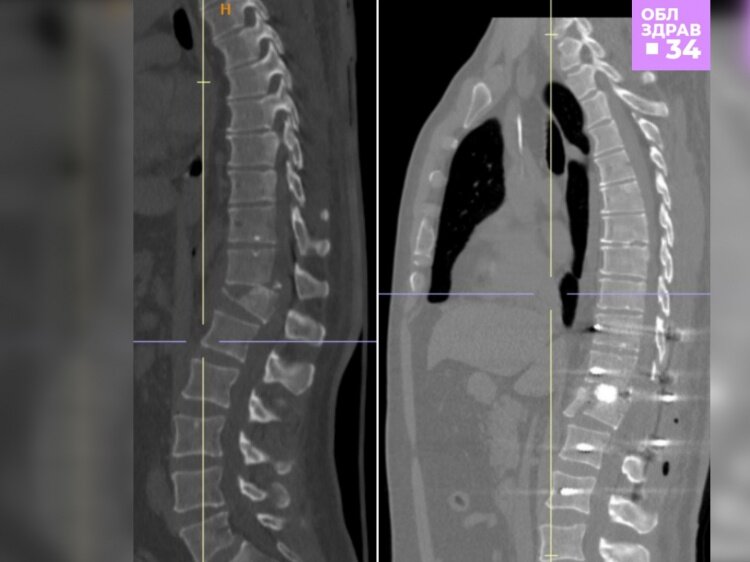

В Волгоградской области медики клинической больницы № 1 буквально собрали по кусочкам позвоночник пациента. Как рассказали Волжский.ру в комитете здравоохранения, мужчина поступил в медучреждение после падения с высоты 4 этажа из-за того, что оборвались промышленные стропы. В результате у него диагностировали производственную кататравму: нестабильный осложнённый компрессионно-оскольчатый перелом позвонка, открытый перелом нижней трети костей левой голени со смещением, тупую травму грудной клетки, закрытый перелом ребер.